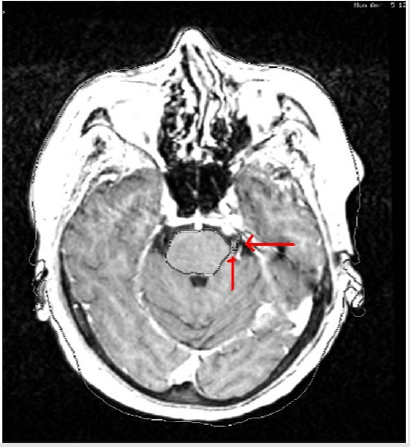

Target volume determination based on CT-only imaging and CT-MR fusion-based imaging was comparatively evaluated. Ground truth target volume defined by board certified treatment team after comprehensive assessment and colleague peer review was identical to target definition using CT-MR fusion-based imaging. Target volume delineation on the planning CT and MR images was optimized by selection of appropriate windows and levels in radiosurgery planning. Contouring accuracy was improved by use of sagittal and coronal images in addition to axial planning CT images. was achieved by use of the Arc Modulation Optimization Algorithm (AMOA) was utilized for optimization of target volume coverage and critical organ sparing. (Figure 1) shows axial planning CT image and (Figure 2) shows the corresponding axial MR image of the same patient with trigeminal neuralgia.